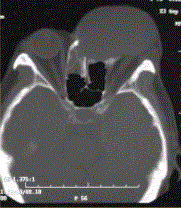

问题 患者男,60岁,头痛,前额部局部隆起。查体:前额隆起处可触及乒乓球样肿块,CT显示如下图。 黏液囊肿的影像学表现,正确的表述有

选项 A.CT表现为鼻窦腔内均匀的浑浊密度影 B.病变边界清楚,窦壁骨质受压变薄,并可见骨质侵蚀 C.MR表现为短T1、长T2信号影 D.MR表现为长T1、长T2信号影 E.病变可累及邻近的眼眶 F.邻近视神经可受压移位 G.MR表现为长T1、短T2信号影

答案 ABCEF

解析 ABCEF